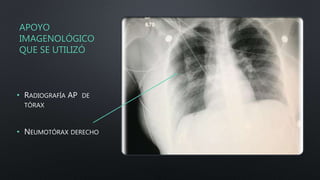

• RADIOGRAFÍA AP DE

TÓRAX

• NEUMOTÓRAX DERECHO

Se le hace una radiografía del brazo derecho que evidencia fractura proximal del húmero y una radiografía de tórax

AP que muestra neumotórax simple del pulmón derecho.